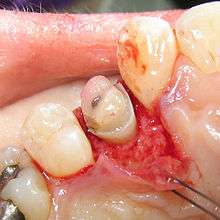

Crown lengthening is a surgical procedure performed by a dentist to expose a greater amount of tooth structure for the purpose of subsequently restoring the tooth prosthetically.[1] This is done by incising the gingival tissue around a tooth and, after temporarily displacing the soft tissue, predictably removing a given height of alveolar bone from the circumference of the tooth or teeth being operated on. While some general dentists perform this procedure, others frequently refer such cases to periodontists.

An alternative to surgical crown lengthening is orthodontic forced eruption, it is non-invasive, does not remove or damage the bone and can be cost effective. The tooth is extruded a couple of millimeters with simple bracketing of adjacent teeth and using light forces this will only take a couple of months. A fiberotomy is performed after crown lengthening and is easily performed by the general dentist. In many cases such as this one shown, surgery and extraction may be avoided if patient is treated orthodontically rather than periodontally.